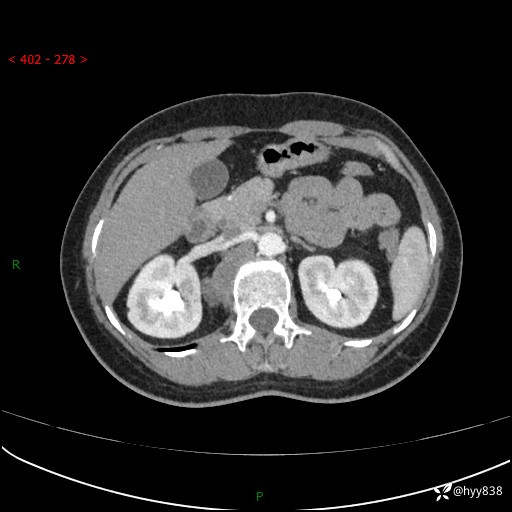

简要病史:患者于1天前因体检发现右旁肾占位,无肉眼血尿,无畏寒发热,无咳嗽咳痰,无腰腹部疼痛不适,无尿频尿急症状,起病来,患者未行特殊治疗,为求进一步诊治,门诊以"右侧腹膜后肿物"收治入院。 发病来患者精神、饮食、睡眠良好,小便如上,大便正常,体重无明显变化。

辅助检查:CT

临床诊断:腹膜后肿物

上腹部CT增强(动脉期+实质期)(外院平扫)